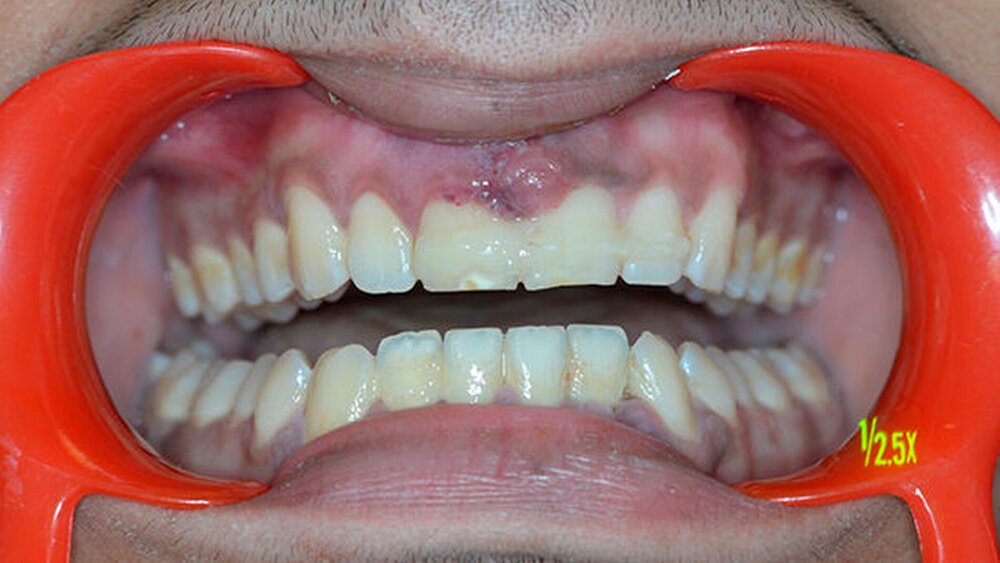

Der Zahn wurde zwei Stunden nach dem Unfall vital replantiert und semipermanent geschient. Die anschließende Abdrucknahme erfolgte unter allergrößter Sorgfalt. Die laborgefertigte Tiefziehschiene schließt die Bereiche der semipermanenten Schiene bis zum Schienenäquator mit ein. Was die Reanastomosierung der Gefäße und Nerven betrifft, ist der Behandler zuversichtlich, reagieren doch auch vital transplantierte Weisheitszähne nach einigen Wochen wieder auf Kältereize.